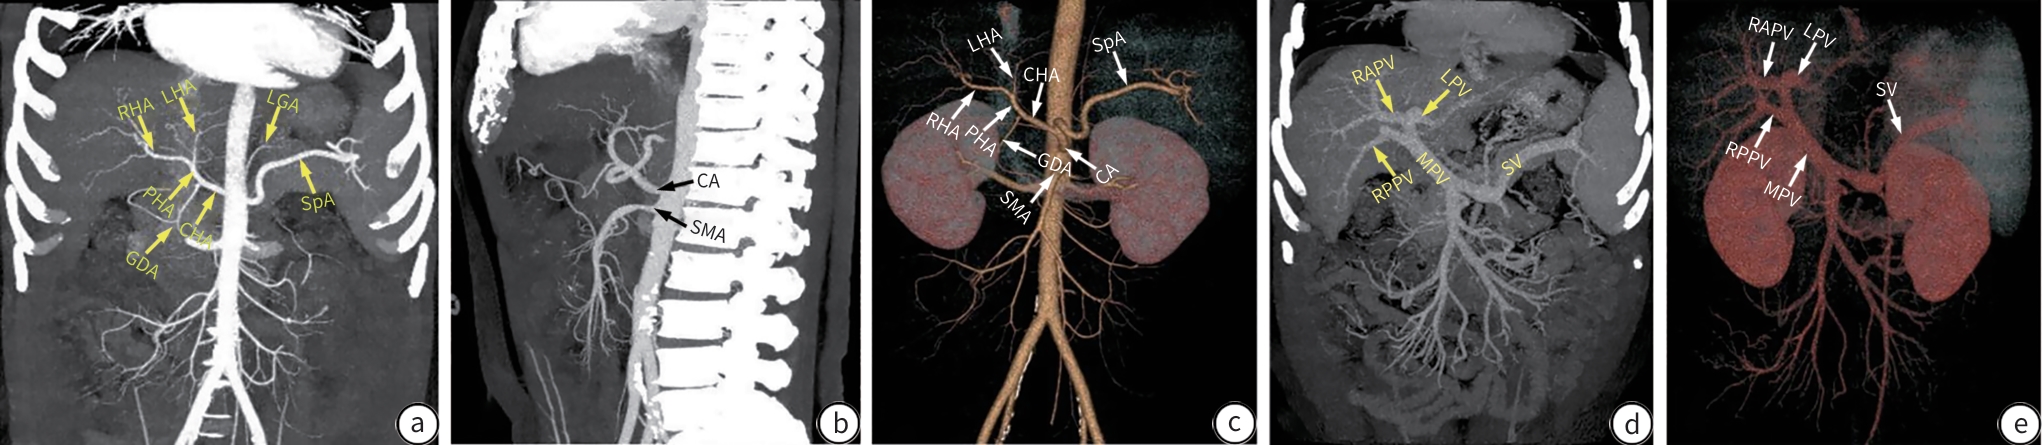

Three-dimensional CT reconstruction of the hepatic pedicle based on the Laennec’s capsule and the development and validation of extra-sheath dissection/occlusion clamp

Zhiyu LIN, Xin XIA, Huan LEI, Yuchuan LUO, Long CHENG, Hongyin LIANG, Tao WANG

2025, 41(10): 2118-2124. DOI: 10.12449/JCH251023

Abstract:

Objective  To investigate the anatomical features of three-dimensional (3D) reconstruction of the hepatic pedicle based on the Laennec’s capsule, as well as its application value in the development of extra-sheath dissection/occlusion clamp and precise hepatectomy.  Methods  A retrospective analysis was performed for the abdominal contrast-enhanced CT data of 100 patients without anatomical abnormalities of the hepatic pedicle in The General Hospital of Western Theater Command from January 2021 to June 2024. The Hisense CAS system combined with the 3D U-net deep learning algorithm was used for 3D reconstruction of the hepatic pedicle at the level of Laennec’s capsule, and the hepatic pedicle was measured in terms of the length, outer diameter, and angle of the main trunk and branches. An extra-sheath hepatic pedicle dissection/occlusion clamp was developed based on the above measurements, and a total of 30 patients scheduled for right hemihepatectomy were enrolled and randomly divided into device group and control group, with 15 patients in each group. The two groups were compared in terms of hepatic pedicle handling time, time of operation, intraoperative blood loss, and the incidence rate of bile duct injury. The independent-samples t test was used for comparison of continuous data between two groups, and the Fisher’s exact test was used for comparison of categorical data between two groups.  Results  The results of 3D reconstruction revealed four variants in the main trunk branches of the hepatic pedicle, with type Ⅰ (left-right branching) accounting for 88% (88/100), type Ⅱ (trifurcation type) accounting for 5% (5/100), type Ⅲ (right anterior branching) accounting for 5% (5/100), and type Ⅳ (special type) accounting for 2% (2/100). The outer diameter of the main hepatic pedicle was 24.10±6.16 mm, the length of the left main branch was 20.59±6.38 mm, and the length of the right main branch was 21.99±7.98 mm. Compared with the control group, the device group had significantly shorter hepatic pedicle handling time (14.10±1.30 minutes vs 17.50±2.00 minutes, t=-5.620, P=0.001) and time of operation (217.00±28.28 minutes vs 241.87±19.49 minutes, t=-2.804, P=0.009). The device group had a significantly lower incidence rate of bile duct injury than the control group (0 vs 20%, P=0.031).  Conclusion  3D reconstruction based on the Laennec’s capsule can accurately display the anatomical variations of the hepatic pedicle. The extra-sheath hepatic pedicle dissection/occlusion clamp developed based on such data can optimize the process of hepatic pedicle management and improve surgical safety, and therefore, it holds promise for clinical application.